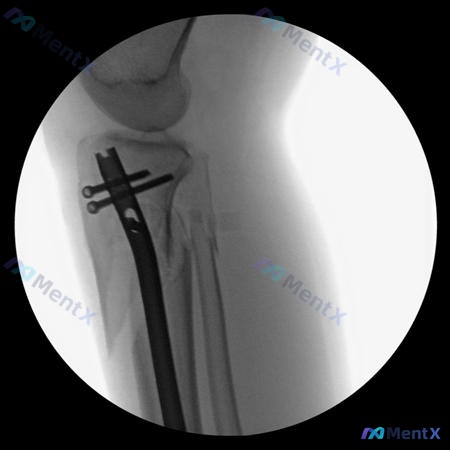

整理了一个车祸致小腿骨折的病例,结合影像资料和分析思路分享一下,重点想聊这类骨折术后常见并发症的预防。 病例基本信息 - 患者:28岁女性 - 受伤机制:行人与车辆碰撞(高能量创伤) 关键影像表现 术前侧位片 - 胫骨:近端明显粉碎性骨折,多块碎裂,移位显著(成角、分离),累及干骺端 - 腓骨:同时...